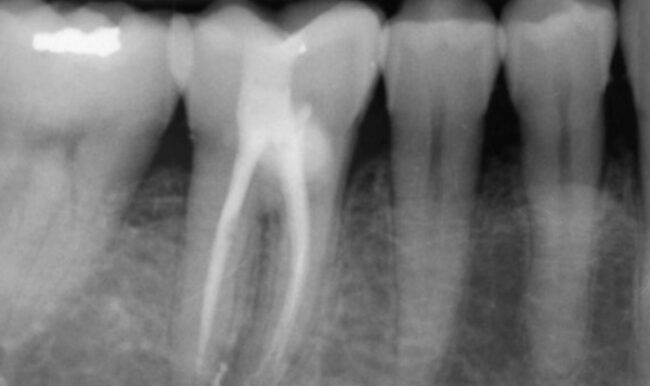

En este caso clínico el doctor Noé Hernández muestra una endodoncia en un diente 47 con un grado de destrucción muy alto. Utiliza el sistema de limas BlueShaper®, ideal en piezas tan deterioradas, y el sistema de activación ultrasónica Z-Activator para lograr una irrigación perfecta.